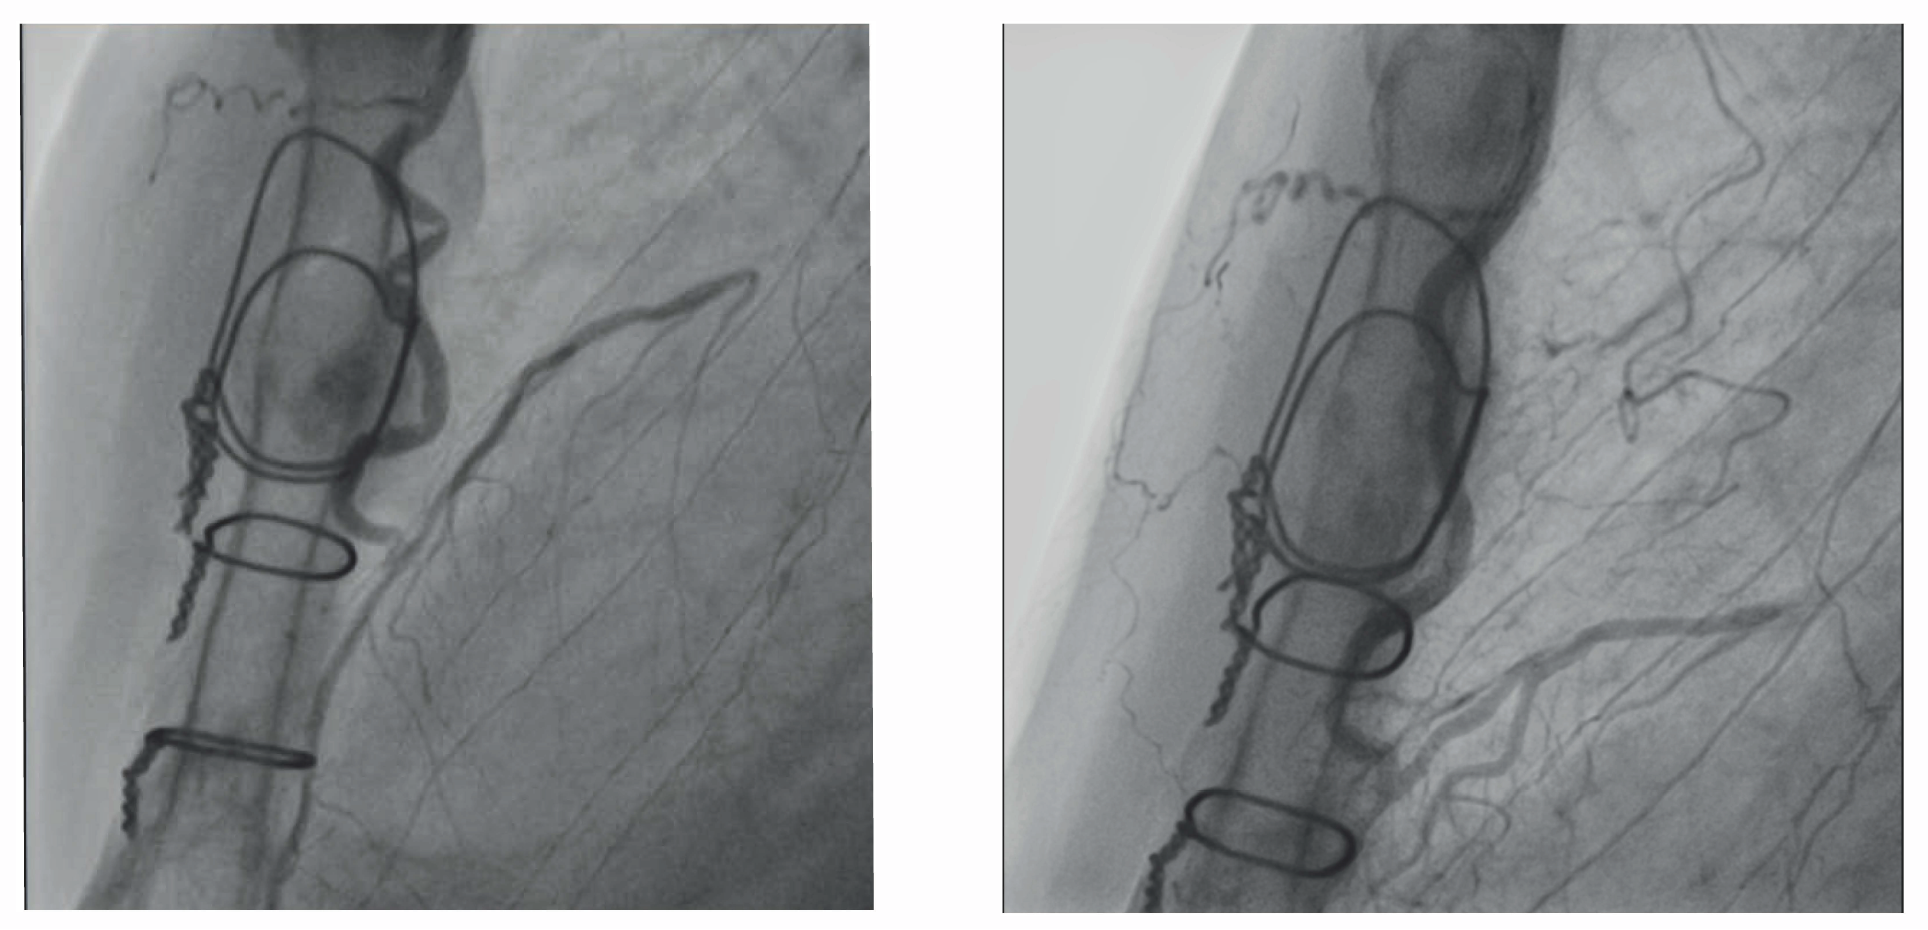

None of the 86 patients had occluded LIMA grafts (grade 0) at discharge or follow-up. The ordinal grading of graft patency improved significantly between early and follow-up CAG (P < .001). Twenty-seven of 37 (73%) patients with Fitzgibbon grade B stenosis resolved to grade A during follow-up (Figure 3). Of the patients with Fitzgibbon grade B stenosis at early CAG, impaired coronary perfusion (TIMI 2 flow) normalized in 3 out of 4, whereas normal coronary perfusion deteriorated in 2.

From October 27, 2010 to October 9, 2014, 131 patients with multivessel disease were prospectively enrolled in the Coronary Hybrid Revascularization Study. A total of 108 patients underwent staged hybrid myocardial revascularization, of whom 96 were treated with coronary surgery prior to PCI, and 11 were treated with coronary surgery following PCI. Twenty-four patients underwent simultaneous hybrid myocardial revascularization. Follow-up CAG was not performed in 13 patients due to refusal of CAG examination (n = 10), treatment of newly diagnosed malignancies (n = 2), and death (n=1). Early and follow-up CAG were performed at median 4 days post-surgery (range, 0-45 days) and at median 12 months post-surgery (range, 8-83 months), respectively. Patient baseline characteristics are summarized in Table 1.14 Formation of the study cohort leading to 86 patients included in final ordinal analysis with sufficient visualization of the LIMA graft on early and follow-up CAG is shown in Figure 1. The study cohort comprised only 17 patients who underwent simultaneous hybrid myocardial revascularization, which was insufficient for separate analysis due to the limited sample size. The distribution of visual graft assessment at early angiography compared to follow-up angiography is depicted in Figure 2.